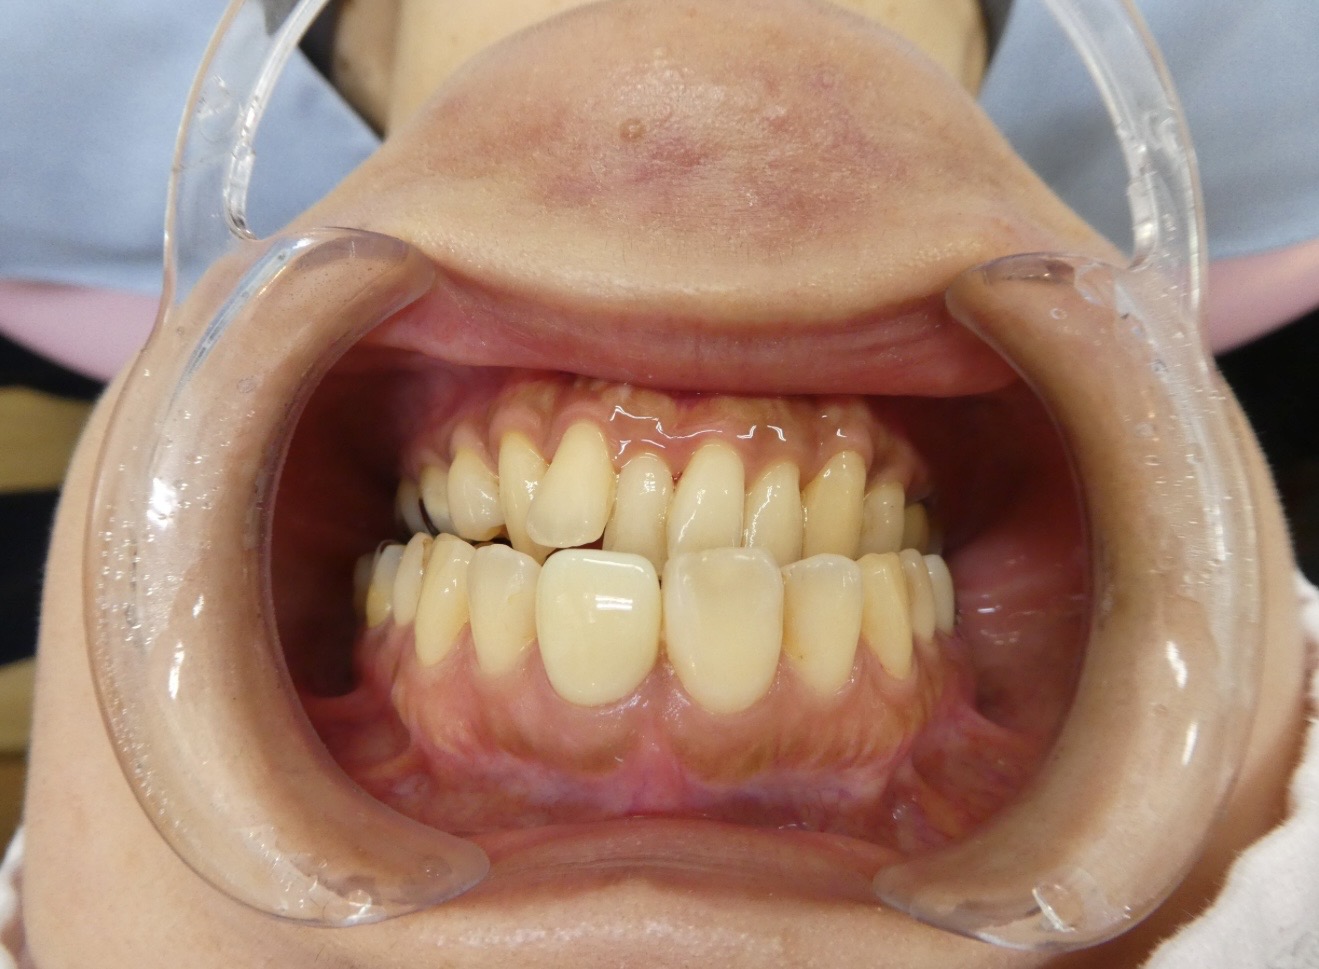

症例1

Before

After

主訴 | 芸能人のように白い歯で、歯並びも整った美しい状態にしたい。そのうえで、治療した部分が長持ちし、しっかりと噛めるようになりたい。 |

治療内容 | 強度に優れ、かつ天然の歯のような自然な色調にもこだわった仕上がりを実現できるよう、ジルコニアセラミック歯を用いた治療をおこなう。 |

治療期間/治療回数 | 1週間~2週間 |

費用 | 120,000円~200,000円(×1本) |

副作用・リスク | ・セラミック治療をおこなうにあたって歯を削ることがあります。 |